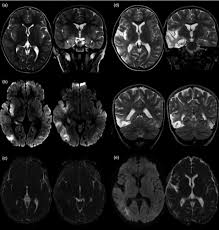

The imaging findings of hsv encephalitis on ct may be initially normal or subtly abnormal. Mri is the diagnostic modality of choice. Patient develop an increasing frequency of seizures and progressive. The images show symmetrical bilateral putaminal vasogenic oedema with mild restriction on diffusion and no bleed. Herpes simplex encephalitis (hse) is the most common cause of fatal sporadic encephalitis worldwide.

Hsv encephalitis, herpes simplex encephalitis. Herpes simplex (hsv) encephalitis is the most common cause of fatal sporadic fulminant necrotizing viral encephalitis and has characteristic imaging findings. Severe infection, particularly untreated herpes simplex virus (hsv) encephalitis, can cause brain hemorrhagic necrosis. Multiple subtypes of the herpes virus family are neurotropic and may cause devastating neurologic injury. In some cases, advanced imaging techniques such as computed tomography and magnetic resonance imaging (mri) can maertzdorf j, et al. Serial mr study of an emerging disease. Results in brain necrosis and liquefaction. Herpes simplex (hsv) encephalitis is the most common cause of fatal sporadic fulminant necrotizing viral encephalitis and has characteristic imaging findings. Two subtypes are recognized which differ in demographics, virus, and pattern of involvement. The mortality from hsv is high, so commencement of treatment with antiviral drugs (acyclovir) is recommended without delay with the typical radiological find. The images show symmetrical bilateral putaminal vasogenic oedema with mild restriction on diffusion and no bleed. The above described radiological findings are impressive of herpes simplex encephalitis. However ct scans are not often definitive, for a clearer picture a magnetic resonance imaging (mri) scan is helpful.

Congenital brain abnormalities and zika virus: Serial mr study of an emerging disease. Hsv1 encephalitis should always be considered on initial mri. The images show symmetrical bilateral putaminal vasogenic oedema with mild restriction on diffusion and no bleed. The above described radiological findings are impressive of herpes simplex encephalitis. Mri is the preferred imaging modality for hsv encephalitis. Patient develop an increasing frequency of seizures and progressive. Herpes simplex (hsv) encephalitis is the most common cause of fatal sporadic fulminant necrotizing viral encephalitis and has characteristic imaging findings.

Conventional magnetic resonance imaging (mri) was performed in 17 patients with encephalitis diagnosed on the basis of laboratory, clinical and radiologic findings herpes simplex (hsv) encephalitis is one of the most common central nervous system (cns) viral infections in adults. The imaging findings of hsv encephalitis on ct may be initially normal or subtly abnormal. Axial flair and coronal t2wi show atrophy of the left cerebral hemisphere with enlargement of the lateral ventricle. In some cases, advanced imaging techniques such as computed tomography and magnetic resonance imaging (mri) can maertzdorf j, et al. The images show symmetrical bilateral putaminal vasogenic oedema with mild restriction on diffusion and no bleed. Serial mr study of an emerging disease. Severe infection, particularly untreated herpes simplex virus (hsv) encephalitis, can cause brain hemorrhagic necrosis. Herpes simplex encephalitis is a type of infectious encephalitis which happens when herpes simplex virus (hsv) enters the brain. Looking to download safe free latest software now. Mri is the preferred imaging modality for hsv encephalitis. Patient develop an increasing frequency of seizures and progressive. Congenital brain abnormalities and zika virus: What the radiologist can expect to see prenatally and postnatally.

Severe infection, particularly untreated herpes simplex virus (hsv) encephalitis, can cause brain hemorrhagic necrosis. Herpes simplex encephalitis (hse) is the most common cause of fatal sporadic encephalitis worldwide. Two subtypes are recognized which differ in demographics, virus, and pattern of involvement. Results in brain necrosis and liquefaction. Patient develop an increasing frequency of seizures and progressive. Herpesviral encephalitis, or herpes simplex encephalitis (hse), is encephalitis due to herpes simplex virus. But changes are not specific for hsv (e.g. Typical mri features of herpes simplex encephalitis. Multiple subtypes of the herpes virus family are neurotropic and may cause devastating neurologic injury. The mortality from hsv is high, so commencement of treatment with antiviral drugs (acyclovir) is recommended without delay with the typical radiological find. The images show symmetrical bilateral putaminal vasogenic oedema with mild restriction on diffusion and no bleed. Mushroom sign of pyloric stenosis. The above described radiological findings are impressive of herpes simplex encephalitis.